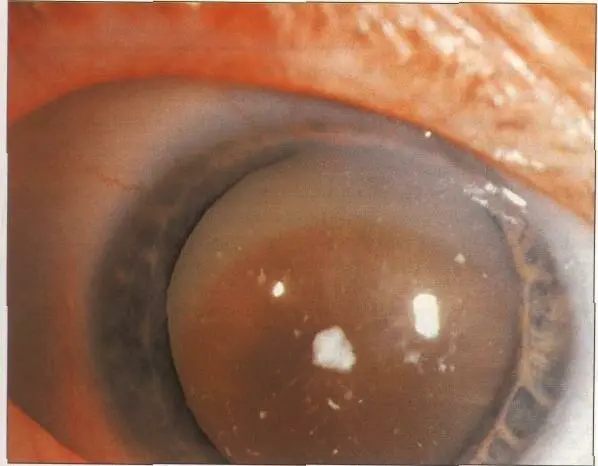

Hypermature cat (morgagnian)

Senile cortical Cat: Mature cat & Hypermature cat